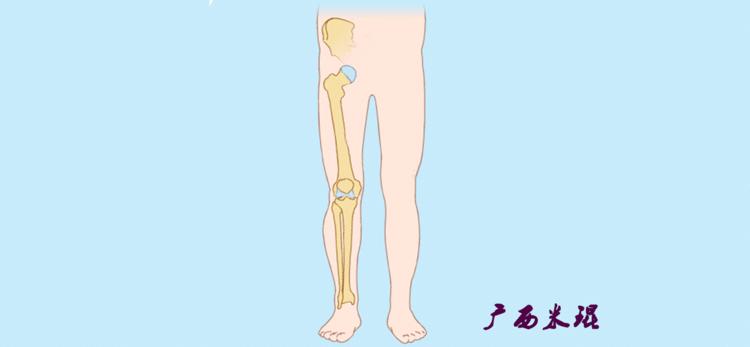

开始接触时可能我们对这些轴有点混乱,通过下面的这张图片就能清楚的了解下肢几个轴之间的关系。

机械轴要分前后位及侧位,站立前后位(也就是冠状面)股骨头中心与踝关节中心的连线通过膝关节中心,这是下肢的机械轴线,也就是下肢力线,常说Mikulicz线。冠状面的力线评估在临床工作中最常用、最基础、最重要。

也就是下肢的负重轴,它是身体的纵轴线,与地面垂直,由于双髋比双踝的距离宽,所以垂直轴与下肢力线(机械轴)存在3°的外翻。